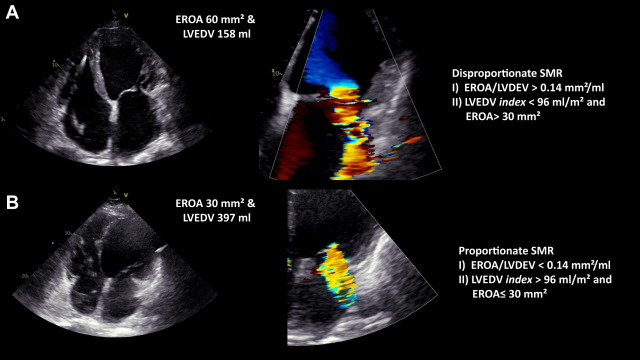

J Am Coll Cardiol. 73: 2506-2517Grayburn P.A. Sannino A. Packer M.

Proportionate and Disproportionate Functional Mitral Regurgitation: A New Conceptual Framework That Reconciles the Results of the MITRA-FR and COAPT Trials.

JACC Cardiovasc Imaging. 12: 353-362

New Evidence Supporting a Novel Conceptual Framework for Distinguishing Proportionate and Disproportionate Functional Mitral Regurgitation.